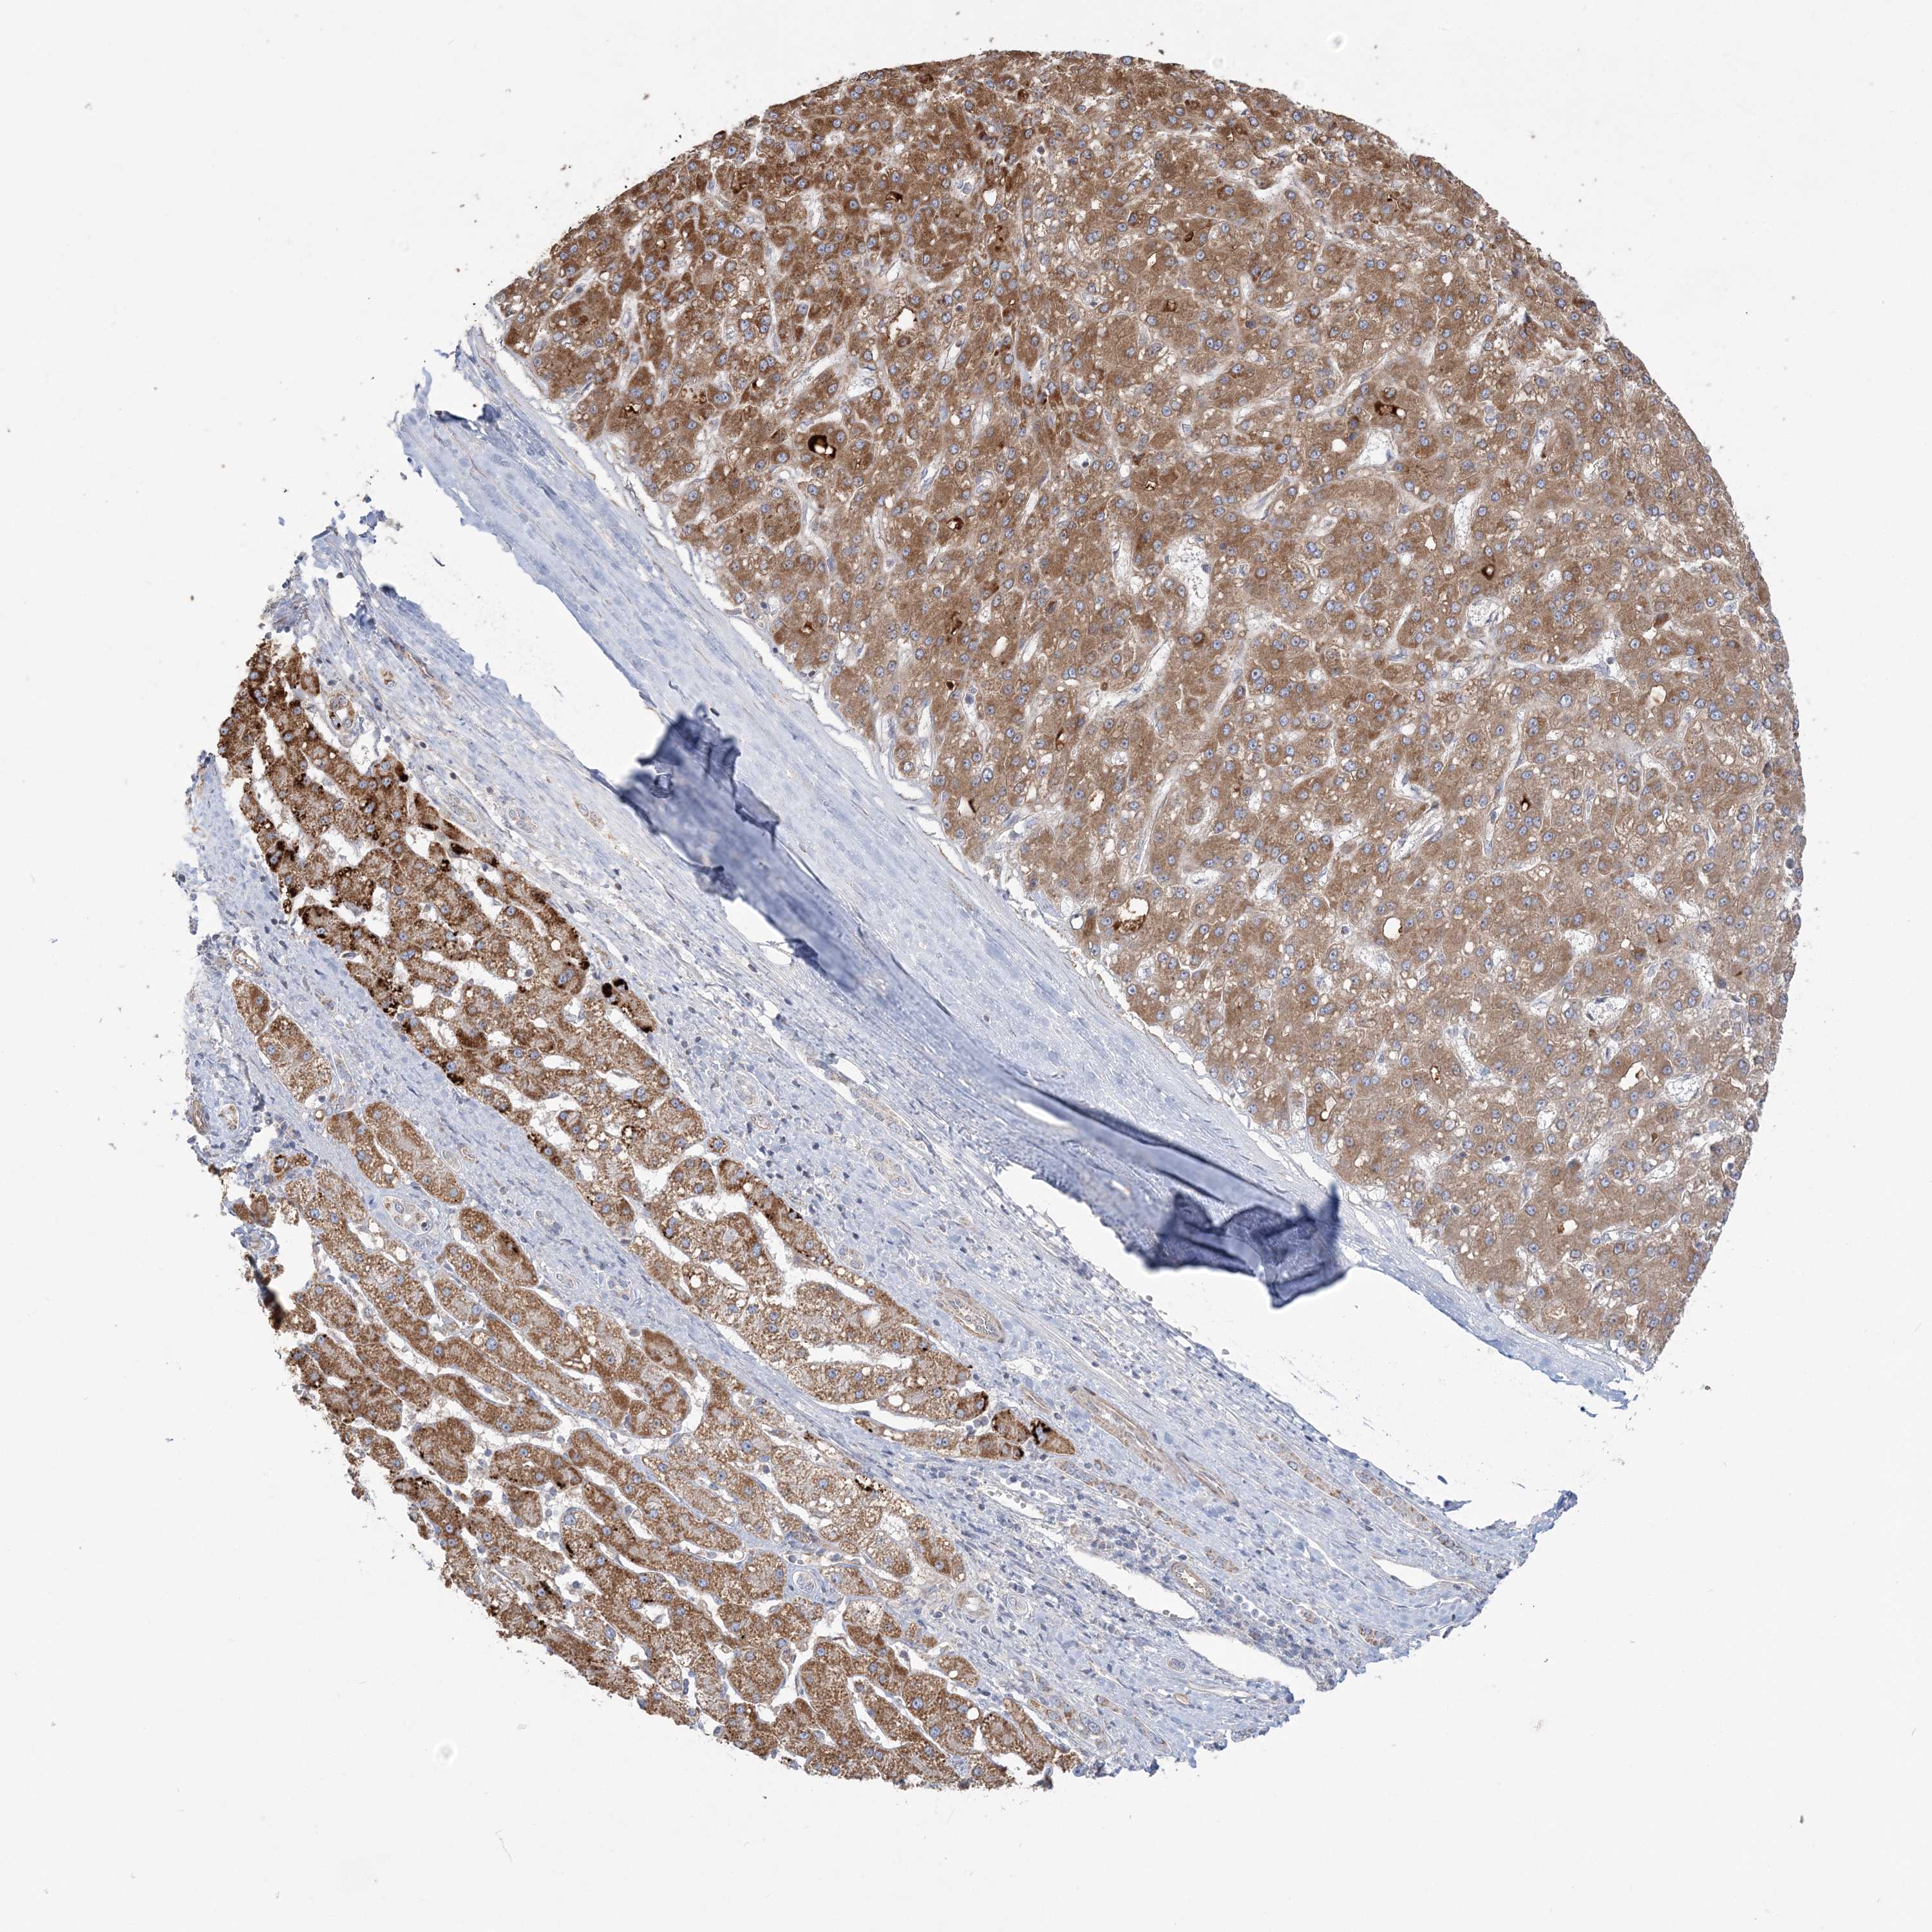

LIVER CANCER - Protein expressioni

A mouse-over function shows sample information and annotation data. Click on an image to view it in a full screen mode. Samples can be filtered based on level of antibody staining by selecting one or several of the following categories: high, medium, low and not detected. The assay and annotation is described here.

Antibody stainingi

Antibody staining in the annotated cell types in the current human tissue is reported as not detected, low, medium, or high, based on conventional immunohistochemistry profiling in selected tissues. This score is based on the combination of the staining intensity and fraction of stained cells.

Each image is clickable and will lead to virtual microscopy that enables deeper exploration of all samples and also displays staining intensity scores, fraction scores and subcellular localization as well as patient and tissue information for each sample.

Antibody HPA036560

Antibody HPA036561

Staining

High

Medium

Low

Not detected

Intensity

Strong

Moderate

Weak

Negative

Quantity

>75%

75%-25%

<25%

None

Location

Nuclear

Cytoplasmic/membranous

Cytoplasmic/membranous,nuclear

Cholangiocarcinoma

Carcinoma, Hepatocellular, NOS